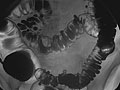

• En un estudio de doble contraste o de contraste con aire, primero se llena el colon de bario y a continuación se drena el bario. Esto deja solo una capa delgada de bario en la pared del colon. El colon entonces se llena con aire. Esto proporciona una visión detallada de la superficie interior del colon. Hace que sea más fácil ver zonas estrechadas (compresiones), divertículos e hinchazón.

El enema de bario, o examen del tubo digestivo inferior, es una radiografía del intestino grueso (colon y recto).

Se detectan uno o varios problemas en el colon, tales como:

• Pólipos o crecimientos en la pared interior del colon.

• Sacos en la pared del colon ( diverticulosis).

• Problemas con anomalías e inflamación (colitis) del revestimiento del colon.